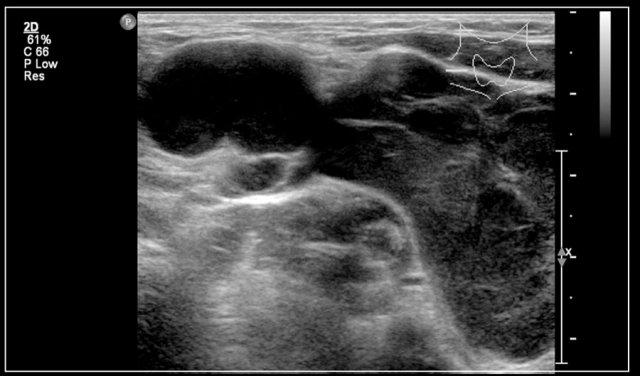

Video cho thấy một khối sưng xuất hiện qua đêm ở một bé gái 13 tuổi.

Một tổn thương giảm âm được nhìn thấy nằm nông so với động mạch cảnh và sâu so với cơ ức đòn chũm.

Không thấy sự di chuyển của nội dung tổn thương khi gõ nhẹ bằng đầu dò.

Khi bé gái được yêu cầu ngồi thẳng, nội dung bên trong xoáy chuyển động.